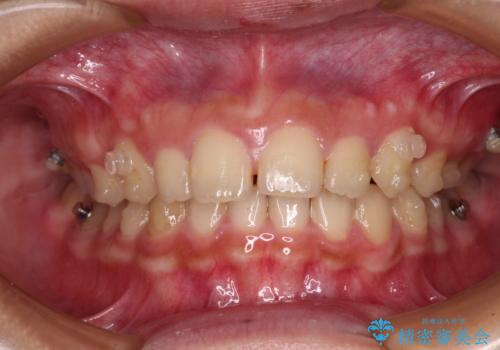

- 深い咬み合わせと上顎前歯の突出感を気にして来院された患者様です。

当院では通常、臼歯の咬合が理想的な位置に対して上顎が前方位にある場合。ワイヤー矯正または補助装置の併用したインビザライン矯正を選択しています。

今回は、できるところまででいいのでインビザライン単体で治療をしたいという希望があったため、インビザラインにて矯正治療を行うこととしました。

インビザラインは、咬合力の強い方ですと、奥歯が歯肉内にめり込んでしまうため、前歯が強く接触してしまうことがあります。

こちらの方は、奥歯はしっかりと噛んだのですが、歯肉にめり込んでしまったことで、歯肉が腫れやすくなってしまいました。